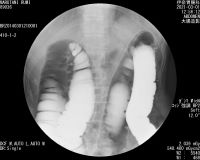

*直腸全摘手術前のレントゲン写真 (伊奈胃腸病院)

2021 3.22 直腸手術